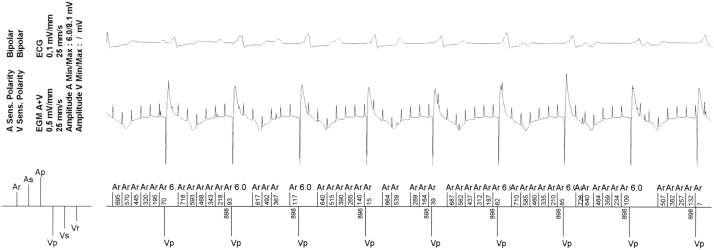

Fig. 2.

Intracardiac electrocardiograms obtained from the pacemaker interrogation showing atrial oversensing due to atrial noise and the consequently activated mode switch.

The patient had DDD pacing when we performed PM interrogation. Diagnosis obtained from the device revealed atrial arrhythmia and mode switches due to atrial tachyarrhythmia. In addition, the asynchronous pacing mode or magnet mode was adjusted to 80 ppm. However, in our patient, VP rate was 898 ms (66 ppm), and no magnet mode was noted in the device log that was consistent with the AMS rate.

This pacemaker is made by Sorin (ELA Medical Symphony DR 2550, ELA Medical, Montrouge, France) and is equipped with a rate response function that is regulated by a minute ventilation sensor. In ELA devices, minute ventilation is measured by using the RA lead with an 8-Hz low-amplitude current. If the RA lead is fractured, the pacemaker automatically increases voltage to maintain the current, and the sensing of this high voltage output prompts an auto-mode switch. In fact, the regular noise in this case was 8 Hz. Therefore, we believe that this was the actual cause of the auto-mode switch.